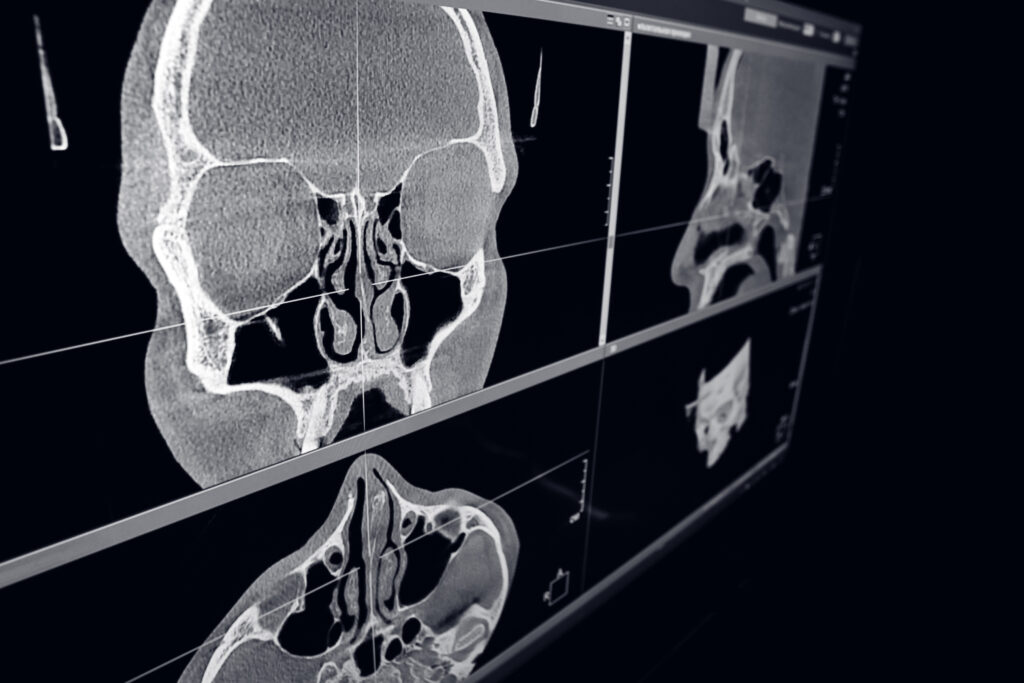

Computed tomography of ENT organs

Cone beam computed tomography in radiation refers to a unique kind of X-ray when a regular facial or dental x-ray…

Computed tomography of teeth and oral cavity

A computed tomography (CT) scan of the jaw deploys the use of advanced technology to view the tissues and bones…

• How do dental diagnostics connect to other medical fields?

Some scans — like dental tomography — offer insights beyond your teeth. They may detect sinus issues, jaw joint disorders, or airway obstructions. This cross-functional value allows for collaboration between dentists, ENT specialists, and other physicians.

• Cone Beam Computed Tomography (CBCT) – for detailed 3D imaging

• Jaw CT and oral cavity scans

A CBCT scan emits more radiation than a standard digital X-ray dental, but still falls within safe exposure levels for medical imaging. Thanks to our diagnostic tools in dentistry, we use only the necessary dose and perform every scan under strict safety protocols. For context: one CBCT = about 1–2 days of natural background radiation. That’s a small price to pay for early diagnosis of dental conditions like hidden infections or bone loss.